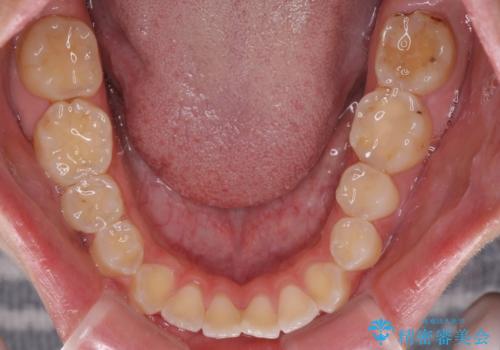

開咬を治す インビザラインによる矯正治療

- 上下前歯の開咬を気にして来院された患者様です。

開咬はインビザラインを用いると有意に改善ができるため、インビザラインによる矯正治療を行うこととしました。

途中1年8ヶ月ほど来院されず、久しぶりの来院後は治療が面倒とのことで、前歯の叢生や隙間に不十分な点が残った状態での終了となりました。